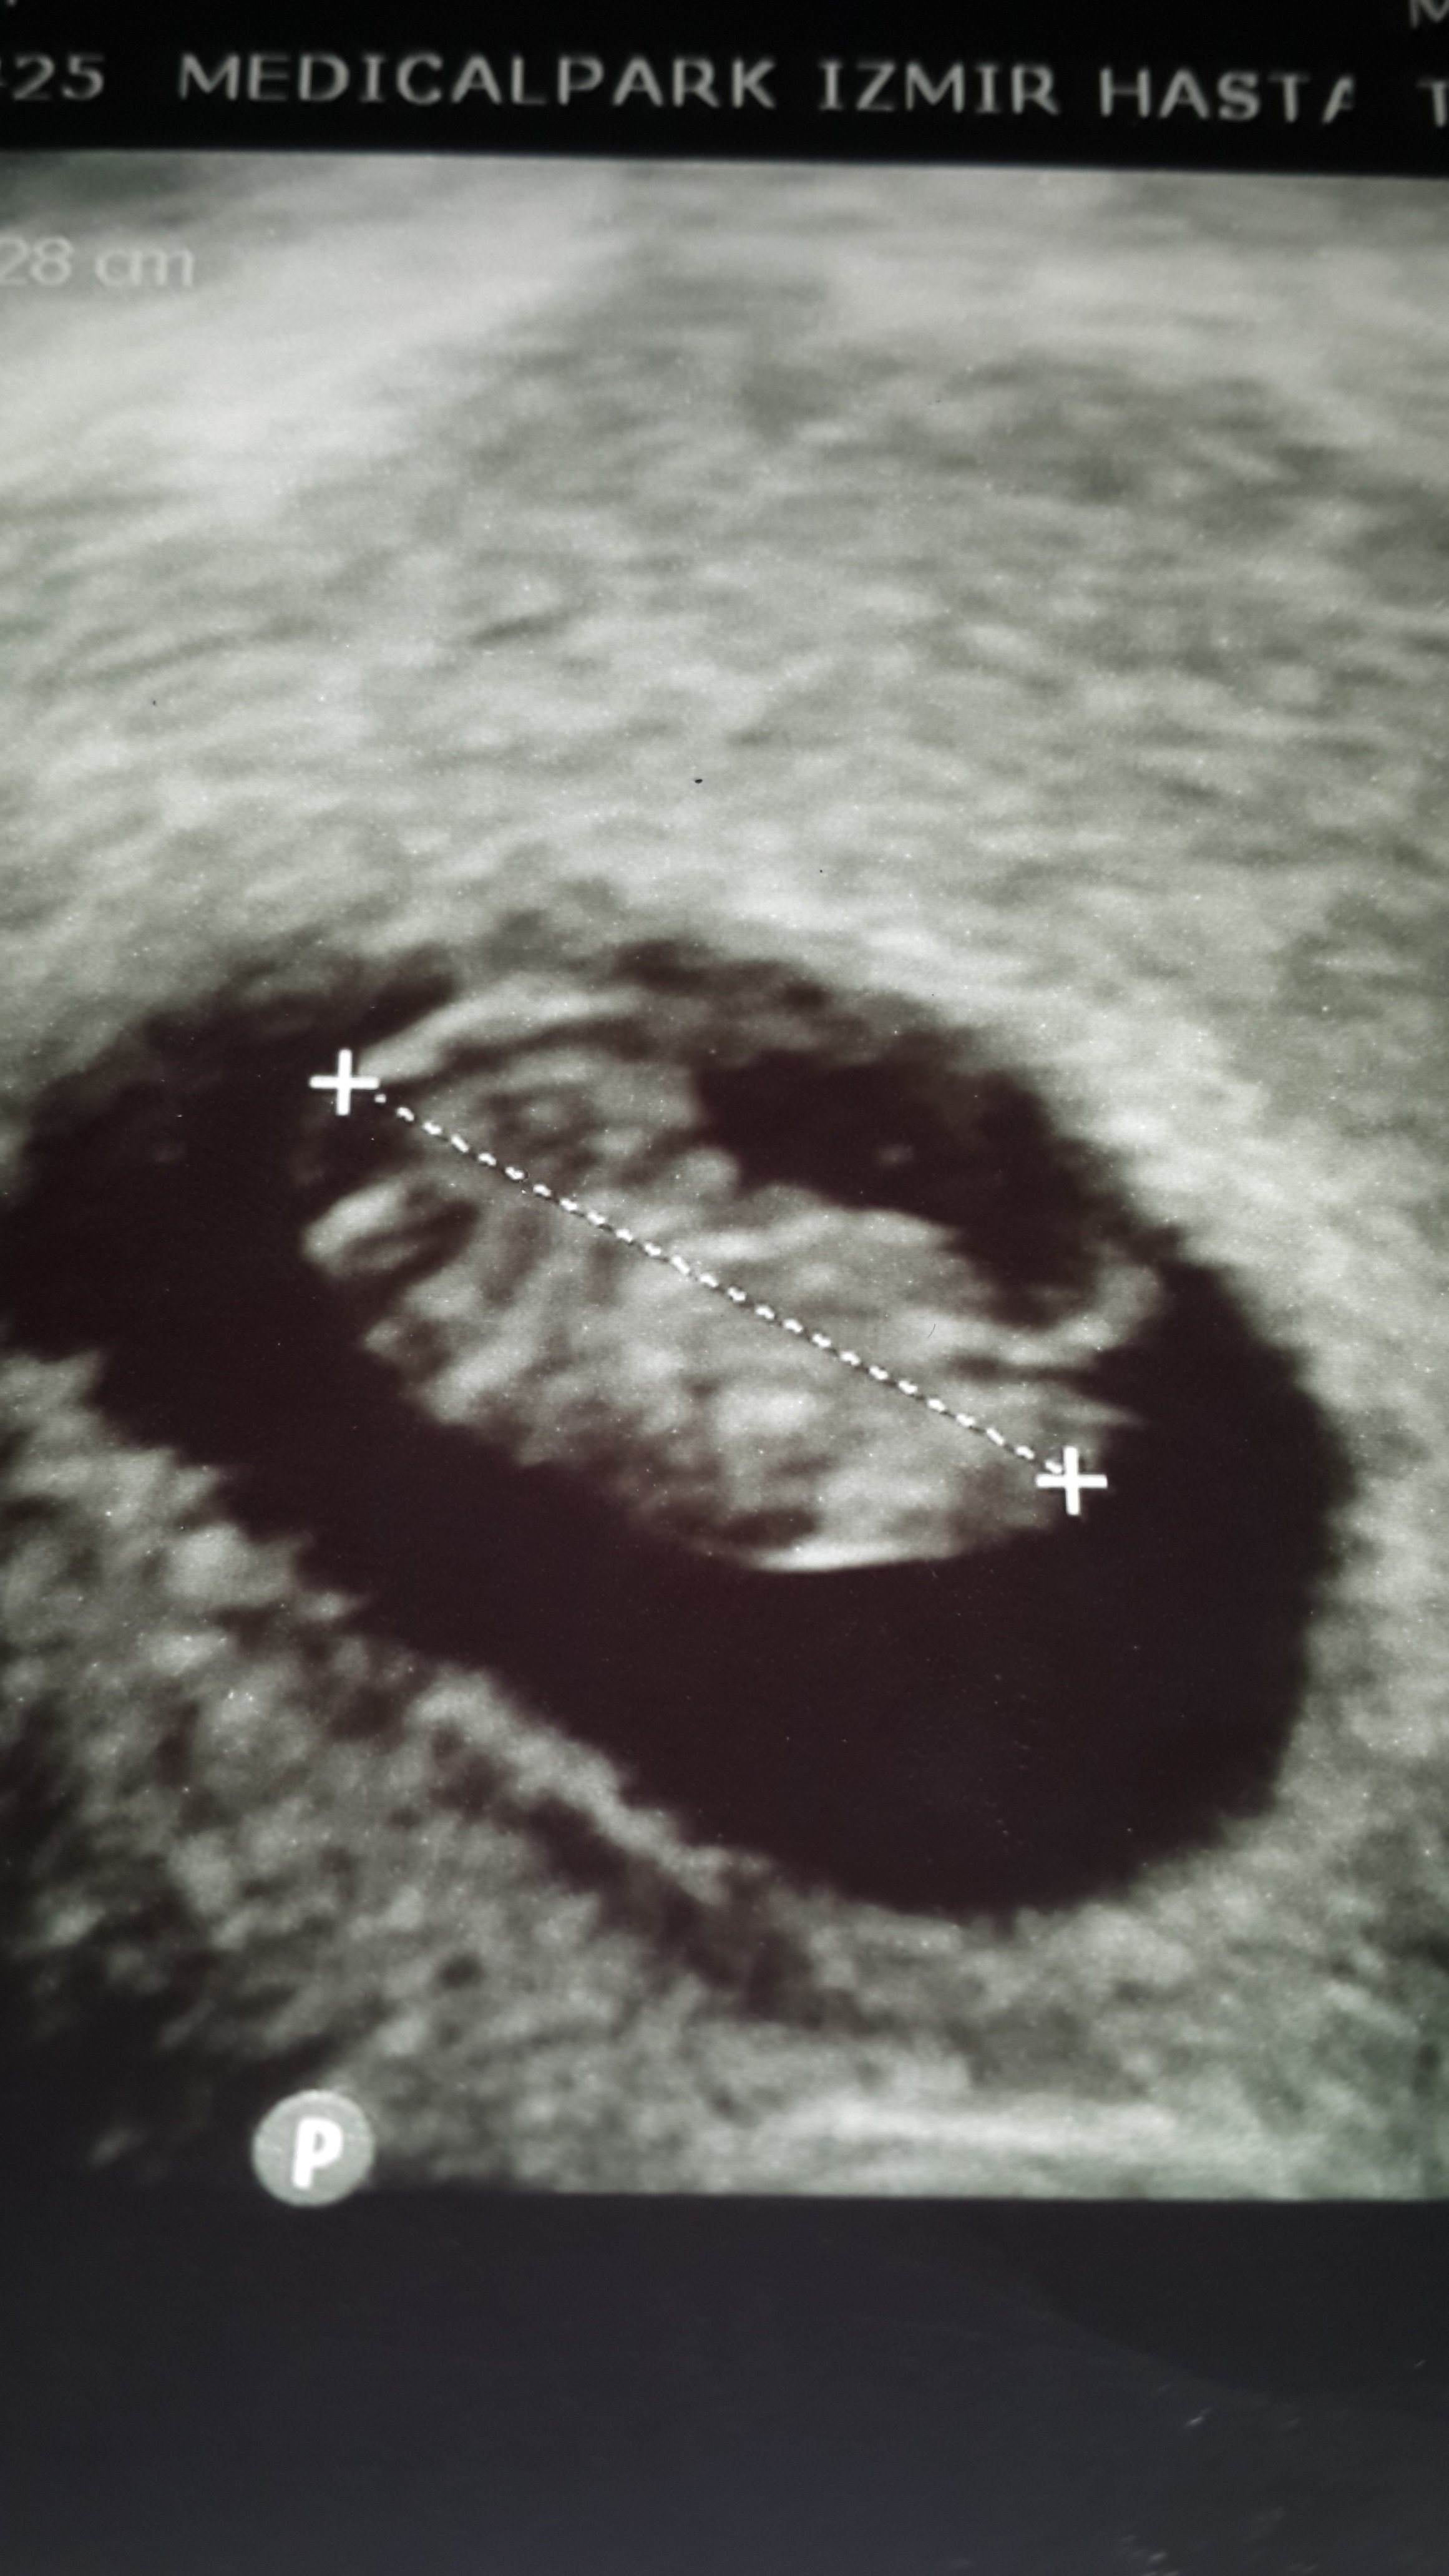

Ekli dosyalar

• IMG_0618.JPG

IMG_0618.JPG

415,9 KB · Görüntüleme: 904